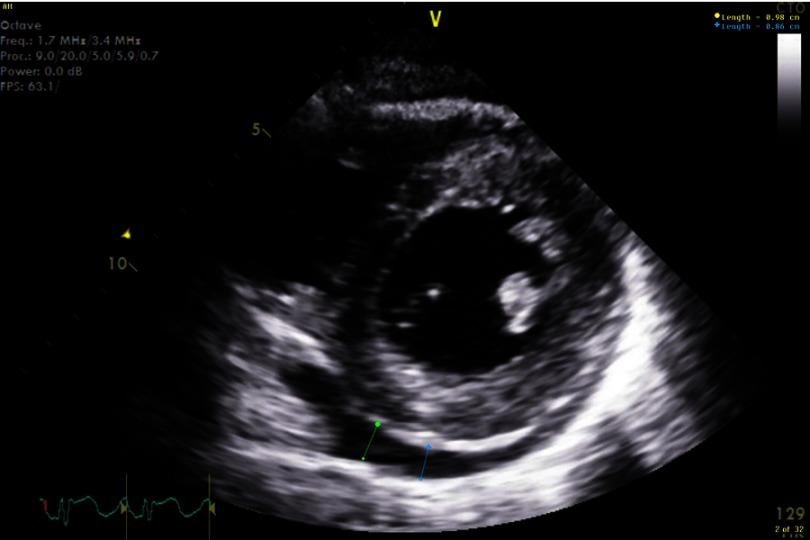

-associated myopericarditis (CAM) has been reported infrequently in the literature. We describe a case of immunocompetent young woman presenting with chest pain, with history of recent travel and diarrhea. Evaluation led to diagnosis of myopericarditis associated with this infection. The patient improved with conservative management. The pathogenesis of CAM remains unknown. Patients present with chest pain, heart failure, pulmonary edema and arrhythmias. Diagnostic evaluation includes EKG, cardiac enzymes, echocardiogram, cardiac MRI and stool culture. Conservative management recommended and routine use of antimicrobial therapy is controversial. CAM is a rare but severe complication of infection. It should be considered as a diagnosis in patients presenting with chest pain with associated gastrointestinal symptoms.